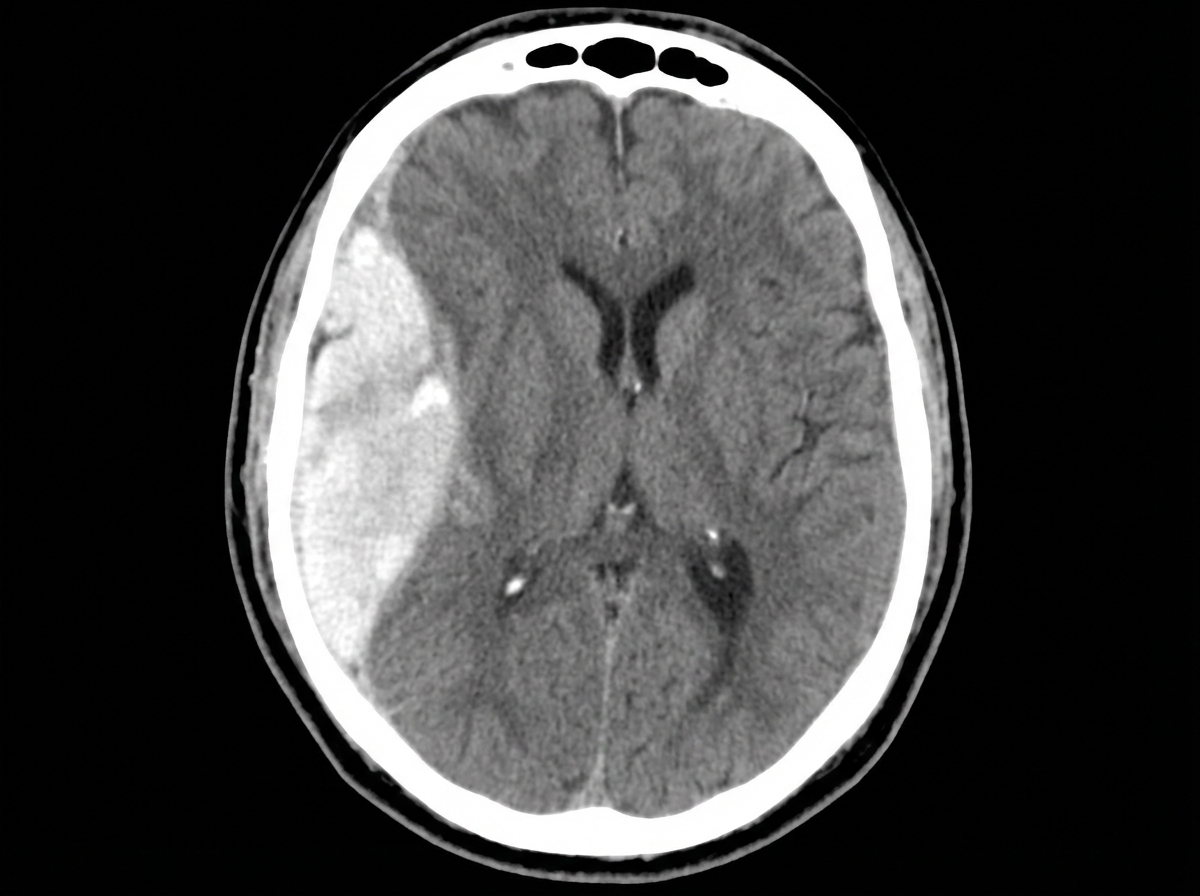

A 47-year-old man is admitted to the emergency room after a fight in which he was hit in the head with a hammer. The witnesses say that the patient initially lost consciousness, but regained consciousness by the time emergency services arrived. On admission, the patient complained of a diffuse headache. He opened his eyes spontaneously, was verbally responsive, albeit confused, and was able to follow commands. He could not elevate his left hand and leg. He did not remember the events prior to the loss of consciousness and had difficulty remembering information, such as the names of nurses or doctors. His airway was not compromised. The vital signs are as follows: blood pressure, 180/100 mm Hg; heart rate, 59/min; respiratory rate, 12/min; temperature 37.0℃ (98.6℉); and SaO2, 96% on room air. The examination revealed bruising in the right frontotemporal region. The pupils are round, equal, and show a poor response to light. The neurologic examination shows hyperreflexia and decreased power in the left upper and lower limbs. There is questionable nuchal rigidity, but no Kernig and Brudzinski signs. The CT scan is shown in the image. Which of the following options is recommended for this patient?

Explanation: ***Surgical evacuation of the clots*** - The CT scan image shows a **biconvex (lenticular) hyperdensity** consistent with an **epidural hematoma (EDH)**, which typically results from arterial bleeding (often from the **middle meningeal artery**). This patient's **"lucid interval"** (initial loss of consciousness, regain consciousness, then deterioration) is classic for EDH. - Given the patient's neurological deterioration (left-sided weakness, pupillary changes, confusion, memory issues) and signs of increased intracranial pressure (hypertension, bradycardia - part of Cushing's triad), urgent surgical evacuation of the hematoma is indicated to relieve pressure and prevent herniation. *Lumbar puncture* - A lumbar puncture is **contraindicated** in the setting of suspected or confirmed **increased intracranial pressure (ICP)**, as it can precipitate **cerebral herniation**. - The CT scan clearly demonstrates a space-occupying lesion, making a lumbar puncture unnecessary and potentially dangerous. *Decompressive craniectomy* - While decompressive craniectomy is a neurosurgical procedure used to reduce ICP, it is generally considered when other measures have failed or in cases of **diffuse brain swelling** or large **intracerebral hematomas** not amenable to simple evacuation. - In this case of a localized epidural hematoma with a clear surgical target, direct evacuation is the primary and most effective intervention. *Administration of levetiracetam* - Levetiracetam is an **anticonvulsant** used to prevent seizures. While seizures can occur after traumatic brain injury, there is no indication that the patient is currently seizing. - Prophylactic anticonvulsants are sometimes used in severe TBI, but addressing the life-threatening hematoma takes **precedence** over seizure prophylaxis. *Administration of methylprednisolone* - **Corticosteroids** like methylprednisolone are generally **contraindicated** in traumatic brain injury (TBI) as studies have shown **worse outcomes** and increased mortality. - They are primarily used for their **anti-inflammatory effects** in conditions like spinal cord injury or vasogenic edema from tumors, not for acute head trauma with hematoma.